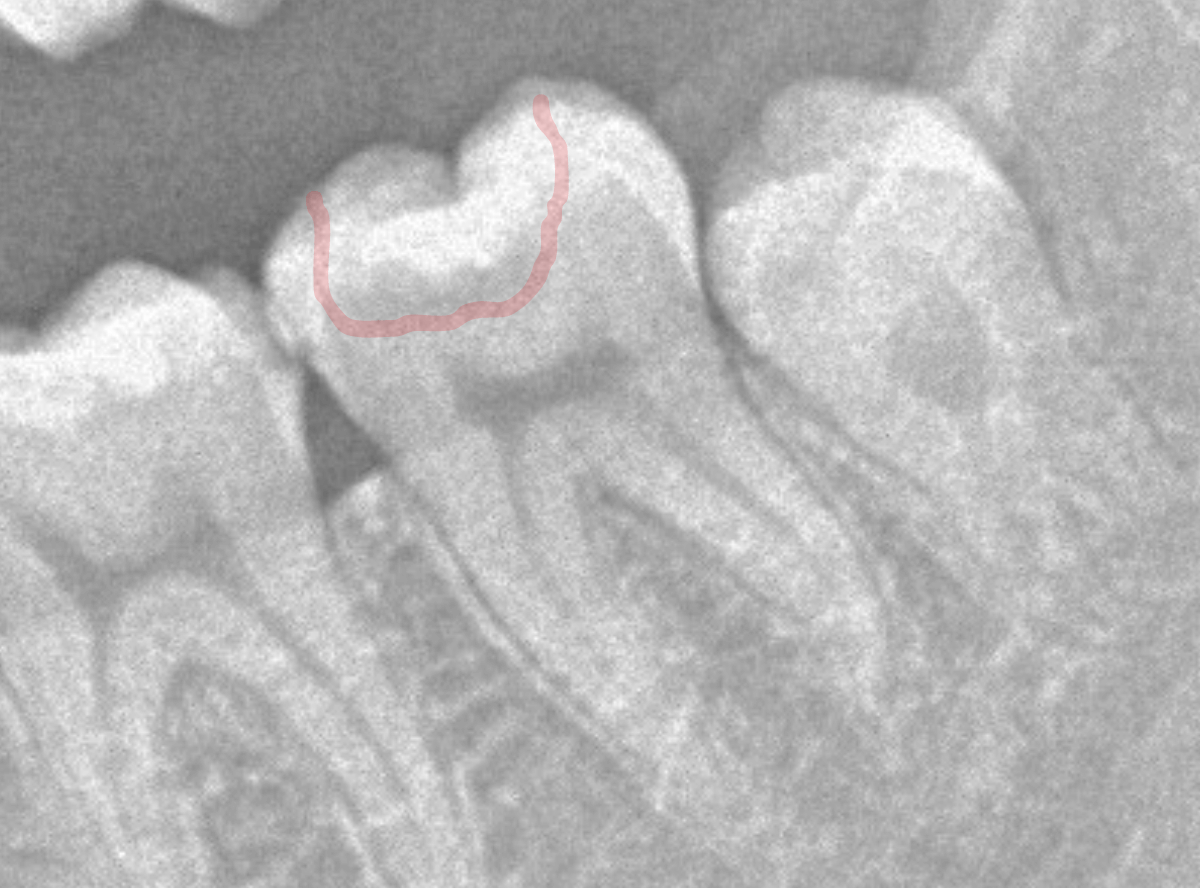

見た目だけでははっきりわかりませんでしたが、レントゲン写真で確認すると、インレーの下で虫歯になっているのがわかります。

インレーを除去して、治療を開始します。

ある程度、虫歯を除去したところで、う蝕検知液で確認します。

赤い部分が虫歯です。

やはり、レントゲン写真で確認した部分が深めの虫歯になっていたようです。